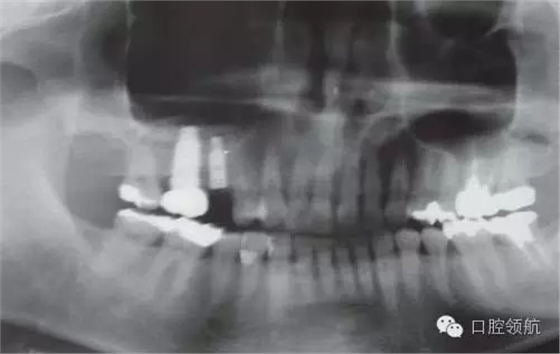

患者10年前,在外院于( 左上第六顆牙)區(qū)行上頜竇底提升術(shù)同期植入種植體,經(jīng)過10年上頜竇內(nèi)生成骨完全吸收消失了(圖1)?;颊叽舜蝸碓菏且驗猷徰? 左上第五顆牙) 不能保存,希望行種植修復(fù)治療。

圖1 術(shù)前牙片。由于上頜竇底黏膜提升植骨術(shù)而在上頜竇內(nèi)生成的骨已完全消失。

圖7 手術(shù)后的曲面斷層片。